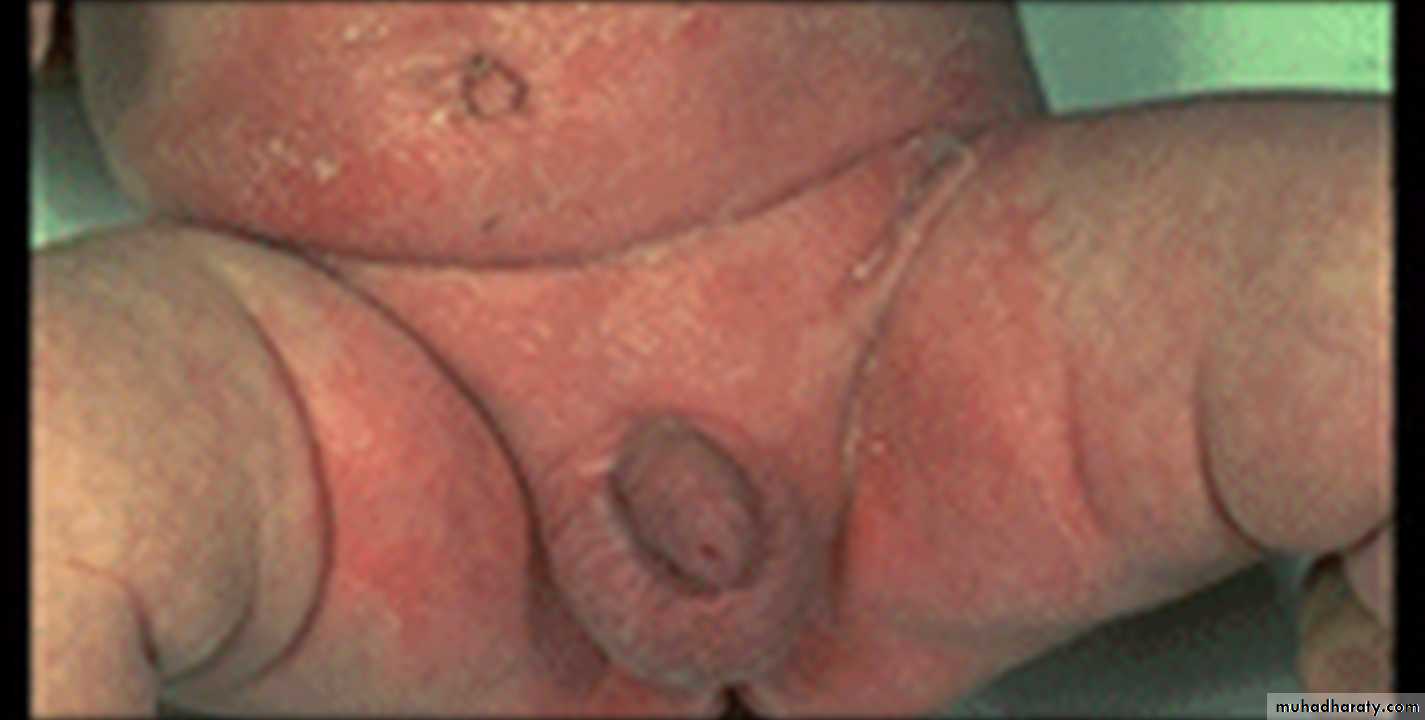

Napkin (diaper) dermatitis

This is a primary irritant effect of body fluids on the skin. The eruption is essentially confined to the area in contact with the diaper.

It is very common in infancy

(but could affect old people who use diapers).

caused by contact with urine & faeces ( bacteria in the last split urea (in urine) to ammonia which is very irritant.

the area (especially convex areas) is mildly to intensely errythematous, macerated ± papules, vesicles& ulcers.

Rx.: avoid using occlusive diapers

keep the area clean &dryUsing abarrier cream such as zinc oxide

use mild topical steiod along with topical antifungalDDx:

1-candidiasis which often accompany it.2-seborrhoeic dermatitis.

3-Tinea cruris.

4-Bacterial infections

5-Inverted psoriasis.